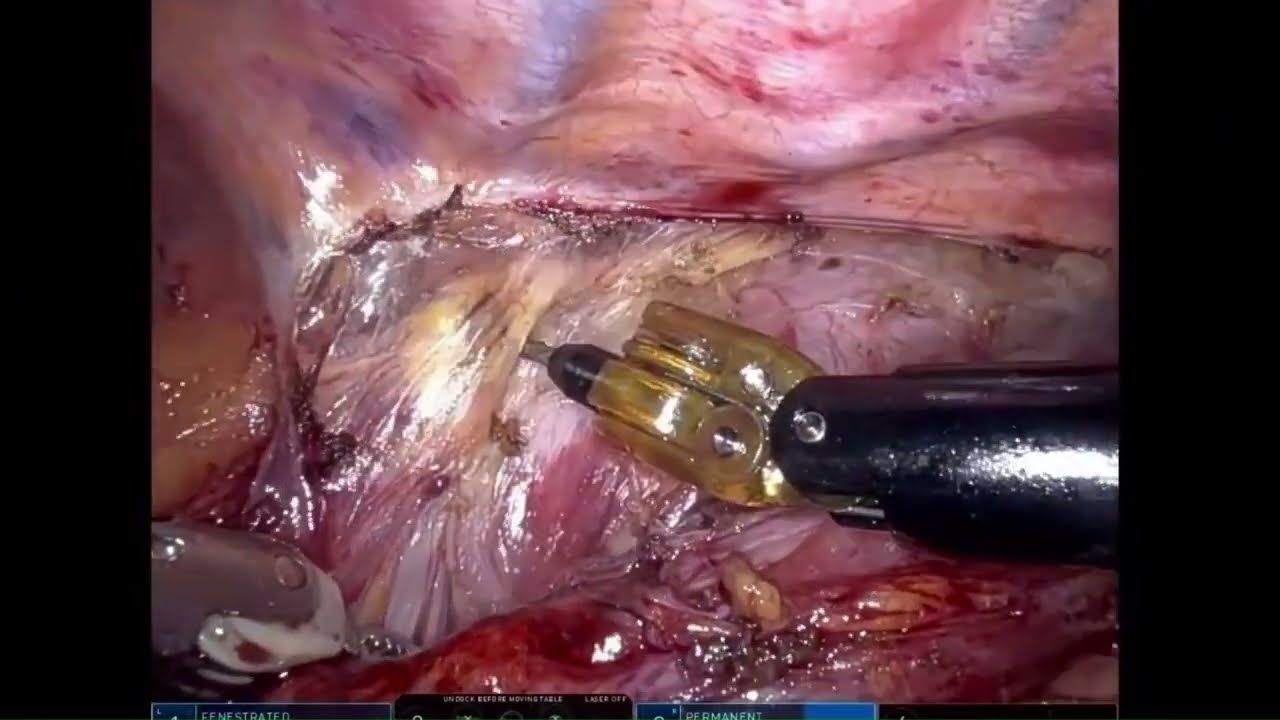

#265 AI-powered real-time annotations during RAPN- Dr. Joan Sureda, Dr. Ketan Badani, Dr. L. Zuluaga